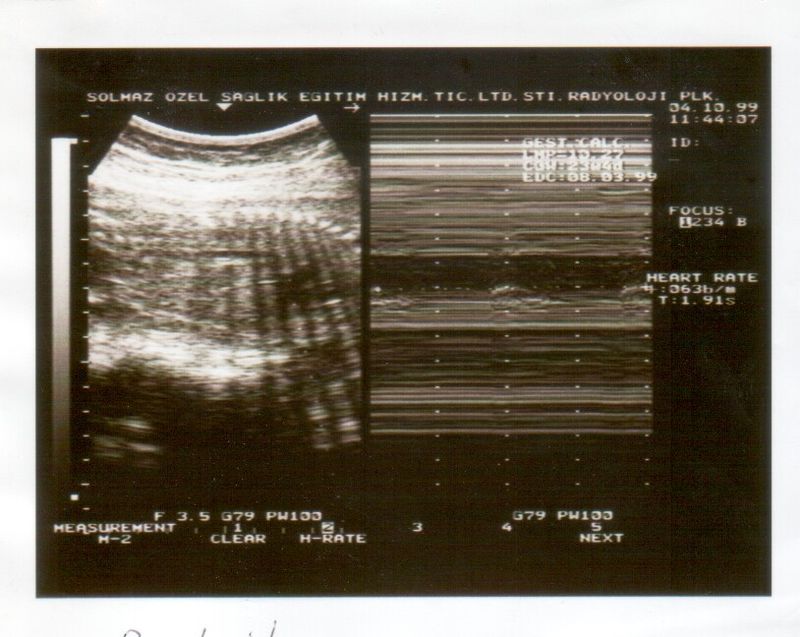

It was during a routine prenatal check-up that Meera's doctor recommended biophysical profile scoring. Intrigued, she learned that this comprehensive assessment evaluates the baby's health across several parameters, including fetal heart rate, muscle tone, movement, breathing, and amniotic fluid levels. This non-invasive test provides an overall score that indicates the baby's well-being, offering crucial insights into any potential issues.

The benefits of biophysical profile scoring extend beyond the emotional realm. It serves as a practical tool for healthcare providers, aiding in the early detection of potential complications. This allows for timely interventions, which can be crucial in ensuring the health of both the mother and the baby. By offering a comprehensive view of the baby's well-being, it also helps in reducing unnecessary medical interventions, thus supporting a more natural birthing process.